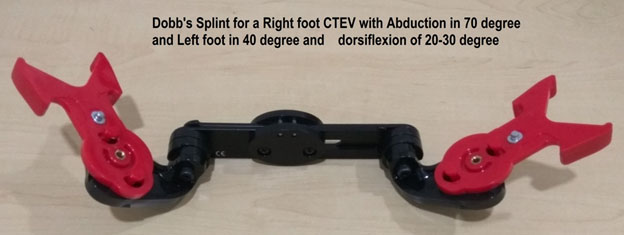

Bracing with Foot Abduction Orthosis- 22-23 hours for three months and later night time bracing for 3-4 years Dennis brown Splint/ Dobb’s splint are orthosis that helps maintain the correction of the deformity. The splints keep the affected foot in a 60-70 degree of external rotation and 20-30 degrees of dorsiflexion. The primary difference between the DB splint and the Dobb’s is the ability to move the feet independently in Dobb’s splint while both feet move together in Dennis Brown splint.